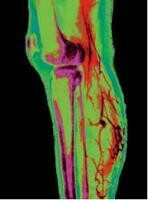

靜脈曲張 | Varicose Vein

Varicose Vein